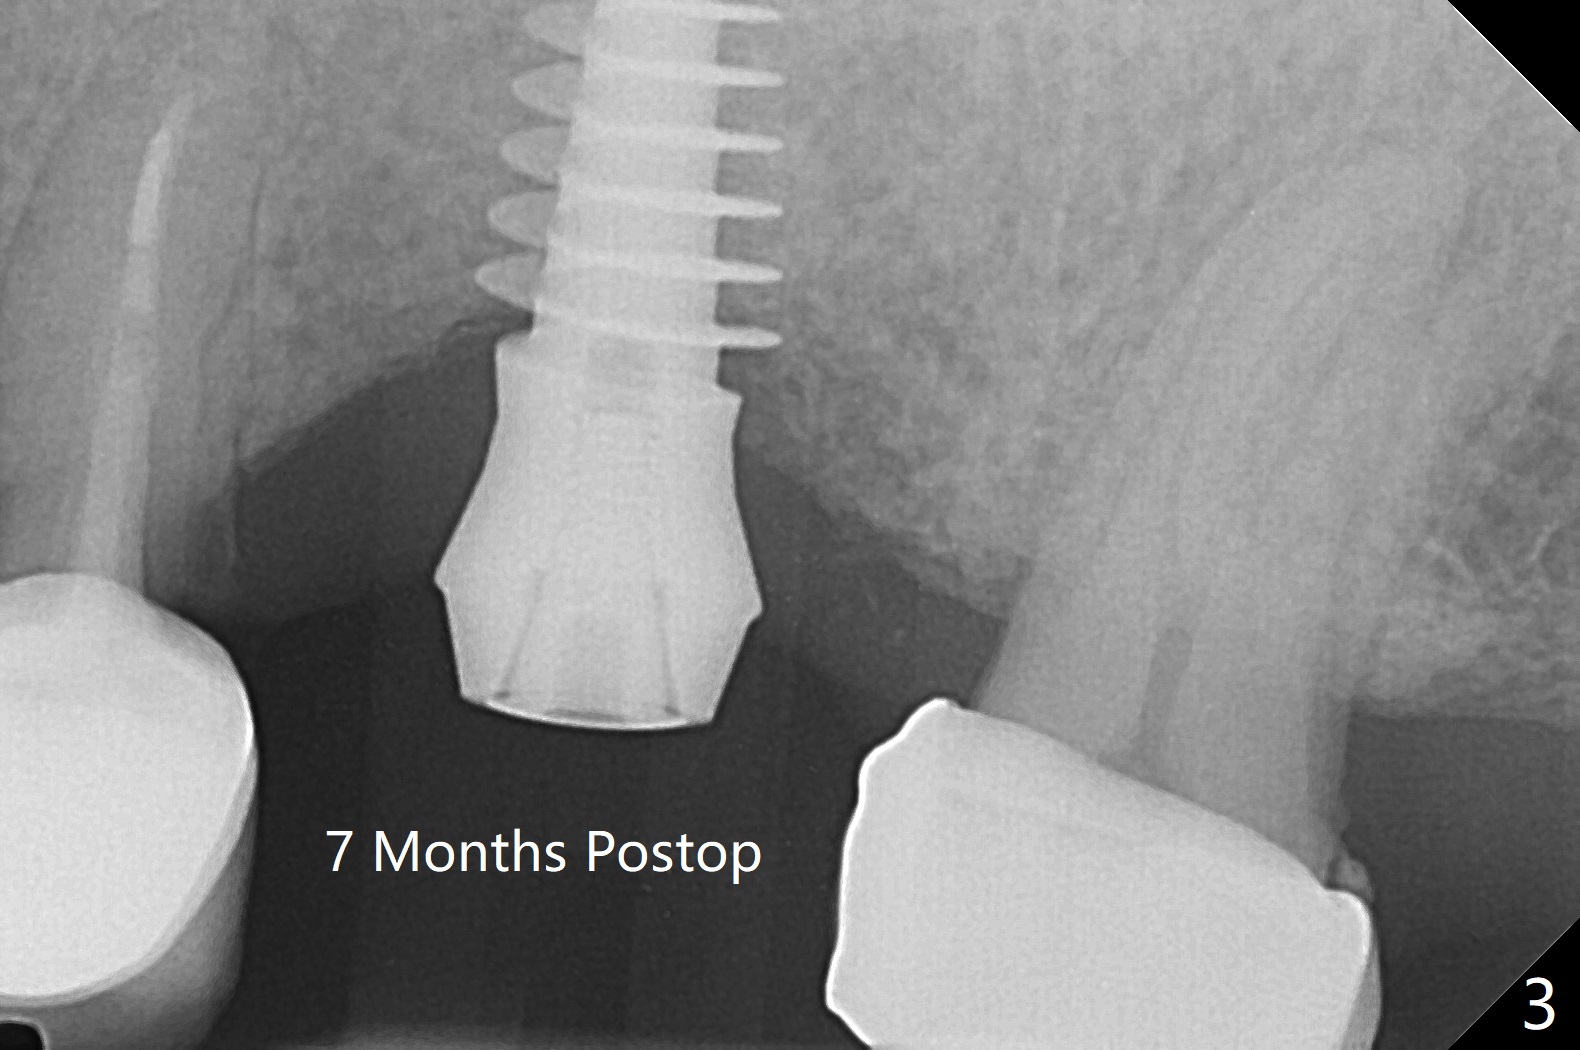

After 4.5x11.5 mm drill (10.5 mm offset) and 5.0 mm tap with guide at #14, the depth of the gingiva is measured 3 mm. A 5.5x9(3) mm Magicore cannot enter the green sleeve and is placed free hand (Fig.1). The margin is slight subgingival mesiodistal. With 3-4 turns, the buccal margin is slightly subgingival, while the palatal one slightly supragingival (Fig.2). The length of the implant could be 11 mm, considering the apical space (double arrows). To prevent periimplantitis, what is the appropriate placement depth coronally? Where does Titanium end? Dr. Wang thinks that the placement level is right. Probably due to underprep, the mesial crestal bone appears to have been resorbed 7 months postop (Fig.3 ^, as compared to Fig.1). The gingiva is healthy. A 4.3x5 mm solid abutment is torqued 20 Ncm for impression. The guide allows the implant to be placed lingual because of buccal concavity (Fig.4), but the coronal end of the solid abutment in the center for restoration (Fig.5 A). The crown is seated partially on the Magicore (M). The temp bond cemented crown is off 8 months post cementation (Fig.6). The bone density increases especially mesial.